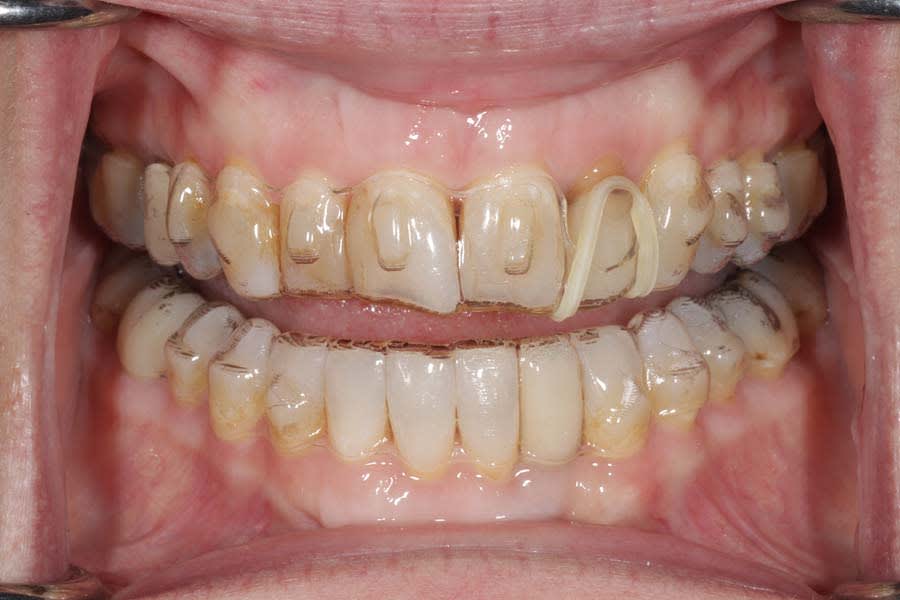

The patient expressed worry about further tooth fractures and dissatisfaction with anterior tooth wear and chipping (Figure 1 and Figure 2). She sought esthetic smile improvement and a comprehensive plan to prevent further breakdown and was open to a systematic approach to data gathering for diagnoses and planning. Historically reliant on single-tooth dentistry, she embraced a thorough approach that involved orthodontics and restorative care to address occlusal and esthetic issues.

Clinical examination identified large restorations (>1/3 intercuspal width) and wear patterns not reported in her dental history questionnaire. Notably, anterior tooth wear was evident, but the patient felt that the wear had not changed in the past 5 years, which was supported by a 12-year historical photograph. This suggested that the occlusal damage could be a result of previous adaptation rather than active breakdown. The report of clenching, however, indicated an ongoing problem, requiring a joint-based reference position.

Functional: Moderate anterior attrition (1 mm to 1.5 mm) was noted, particularly on teeth Nos. 6 through 9 and 24 through 27, with no significant posterior wear or abfraction lesions. The patient reported slow progression of attrition on her front teeth that had stabilized over the past 5 years, corroborated by a historical photograph. Temporomandibular joint (TMJ) evaluation revealed a 40 mm maximum opening with slight right deviation, asymmetrical lateral movements (8 mm right and 11 mm left), and no pain or joint sounds. She had facial asymmetry as her chin point was 2 mm right of center. CBCT imaging showed a non-reducing anteriorly displaced disc in the right TMJ with osteophyte formation and reduced cortical bone, contrasting a normal left TMJ (Figure 6). Occlusal dysfunction was suspected due to her aberrant chewing pattern, which resulted in unilateral attrition and clenching. Her initial deprogramming identified the first contact on tooth No. 2 with a slide into maximum intercuspation, supporting an occlusal dysfunction diagnosis.